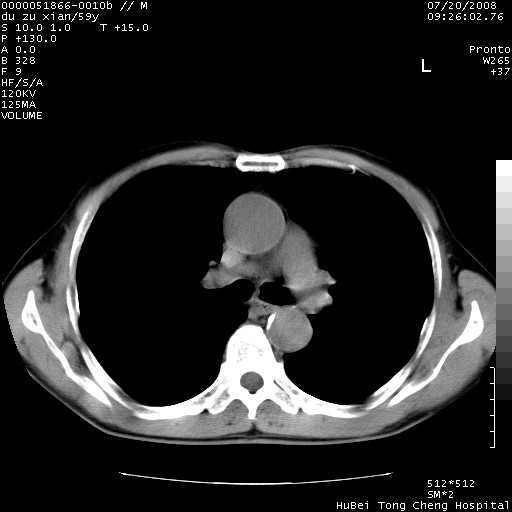

以下是引用宇宙ct在2008-8-25 23:21:00的发言:[br]右肺周围性肺癌并肋骨转移,纵隔淋巴结转移。

以下是引用zsl6918在2008-8-25 22:40:00的发言:[br]右肺周围性肺癌并肋骨转移,纵隔淋巴结转移。

以下是引用zy_zj在2008-8-26 15:24:00的发言:[br]单从病变本身,我倾向良性炎性病变,但肋骨转移了,所以说是考虑右肺周围性肺癌并肋骨、纵隔淋巴结转移可能性大。